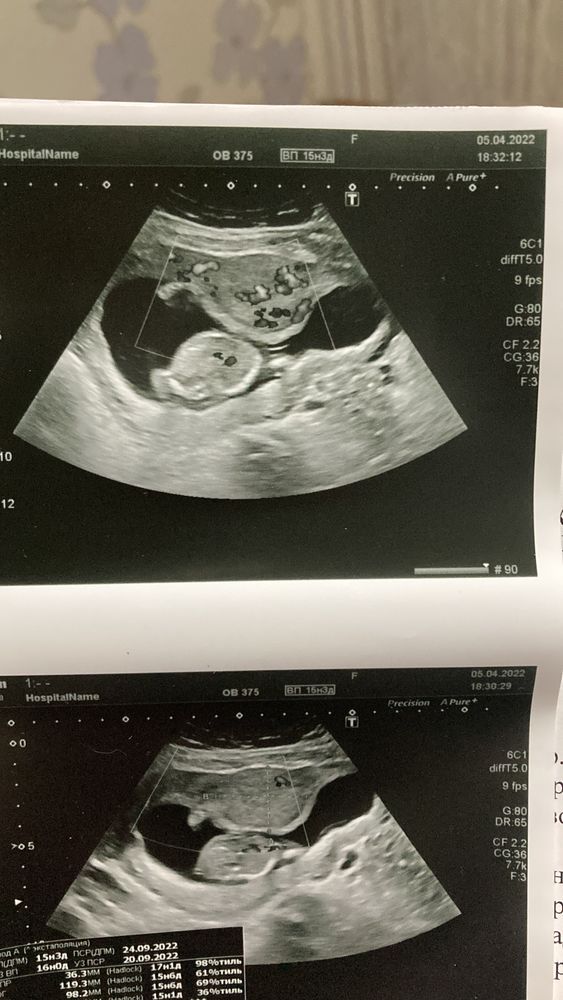

Kate, Изображение Это из городской больницы сегодняшнее узи

Извините, не совсем понимаю где миома на снимке? Просто у меня тоже крошечная и до 2ого скрининга ее пока не нашли. До Б видели. И то, что давит на малыша по центру, это что? У меня так же🙈Ох, я сапожок, ничего в этом УЗИ не понимаю.

Александра, вот на снимке как раз то,что они называют миомой и гипертонусом,но определится не могут